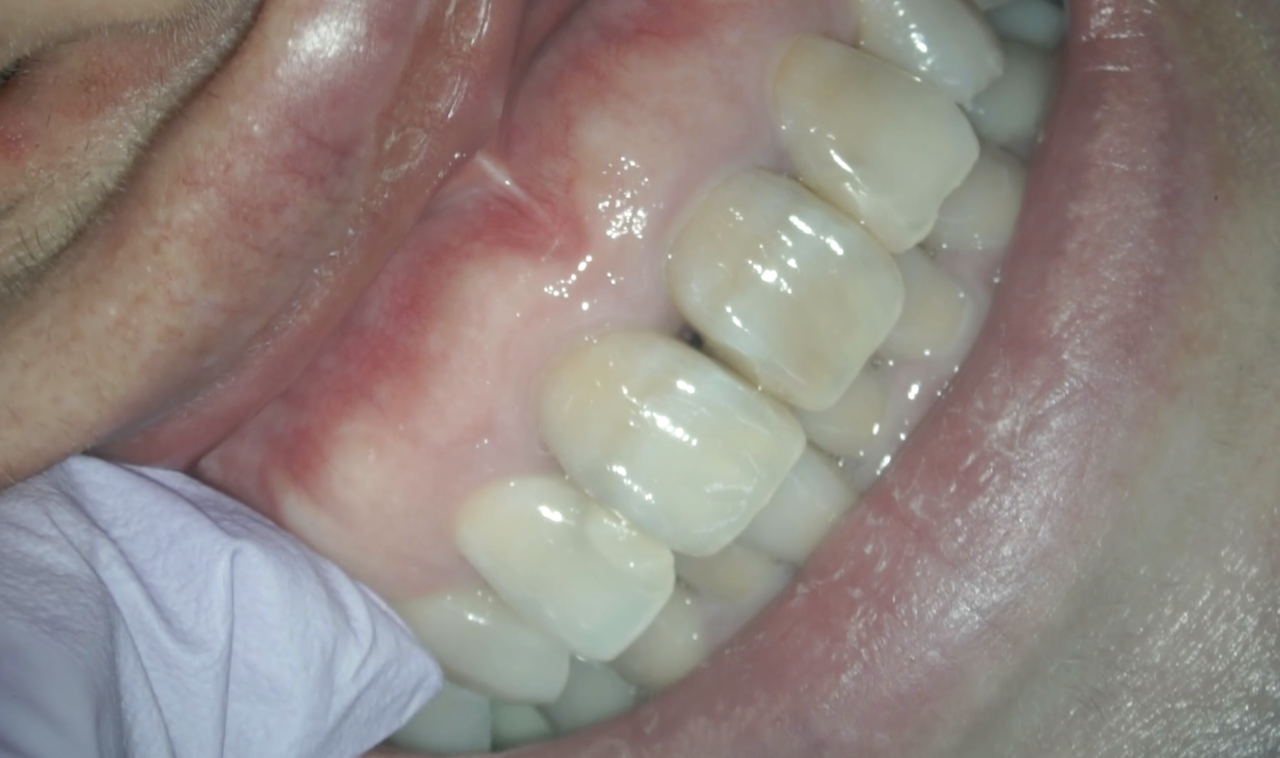

この後、患者さんの都合で早いが2日後に抜糸に来院された。

見た目は痛々しい。。。

うっすらだが瘢痕が見える程度で審美的には気にならないという。